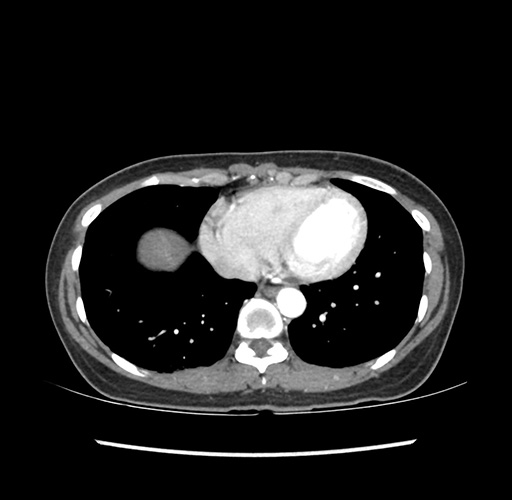

Imaging Analysis

Look through the patient's CT scan to identify any areas of concern for the necessary procedure.

Based on your CT findings, which issue(s) would give reason for "planned slowing down moment(s)" in this case?

Considering a standard left lateral sectionectomy procedure, what step(s) of the operation would you do differently in this case ?